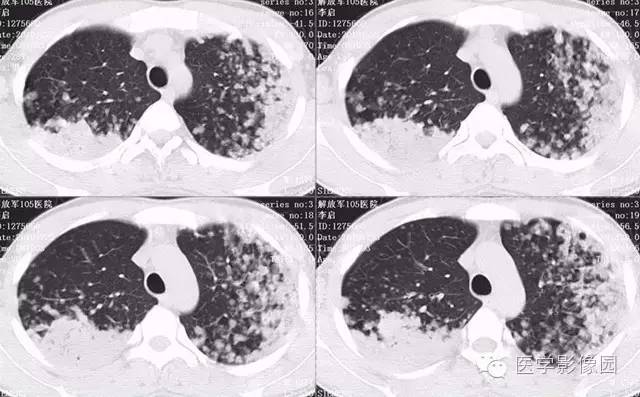

弥漫性肺泡细胞癌1例CT影像表现

病理结果:弥漫性肺泡细胞癌

弥漫性肺泡癌的主要临床及CT表现:临床表现无明显特征, 随着病情的进展, 咳嗽、 咳白痰、 进行性气促。CT表现 为病变分布有两种情况:病变累及一个肺段或肺叶;病变广泛分布于两肺。可归纳为5个特征性征象:蜂房征;支气管充气征;磨玻璃征;血管造影征;两肺弥漫分布的斑片状与结节影。